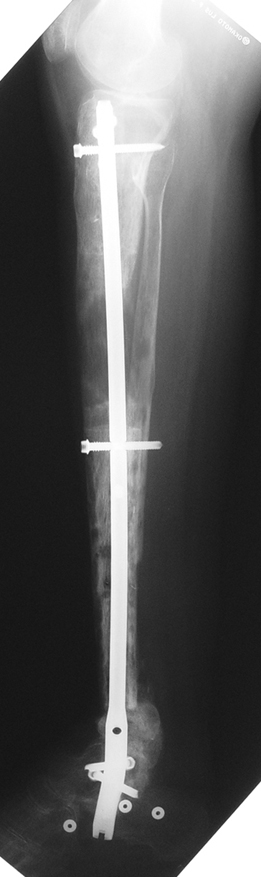

Kaynamayan kemik uçlarının çıkartılması, damarlı fibula veya fibula grefti, damarlı kas greftleri ile birlikte internal fiksasyon uygulamaları, elektrik stimulasyon gibi uygulamalar kaynamamada bir şeçenektir. Fakat kısalık ve deformite gibi ek patolojiler tedavisinde kısıtlı kalmaktadır. İlizarov eksternal fiksatörü ile uygulanan distraksiyon osteogenezi uygulamaları ile birlikte yapılan psödoartroz sahasından akut kısatma ve aynı kemikteki diğer segmentten uzatma yapılmaktadır.

Ilizarov ve arkadasları, kendi geliştirdikleri yöntem ve fiksatörle, aynı anda, hastanın günlük aktivitelerini kısıtlamadan, eklem fonksiyonlarını koruyarak kaynamayı basarmıs,deformiteyi düzeltmis, uzunlugu yeniden sağlamıstır. Bu teknik sayesinde kemik defektlerinin kapatılması ve enfeksiyon gibi hastaya morbidite getiren ek patolojiler giderilmiş aynı zamanda kısalıkta telafi edilmiştir.